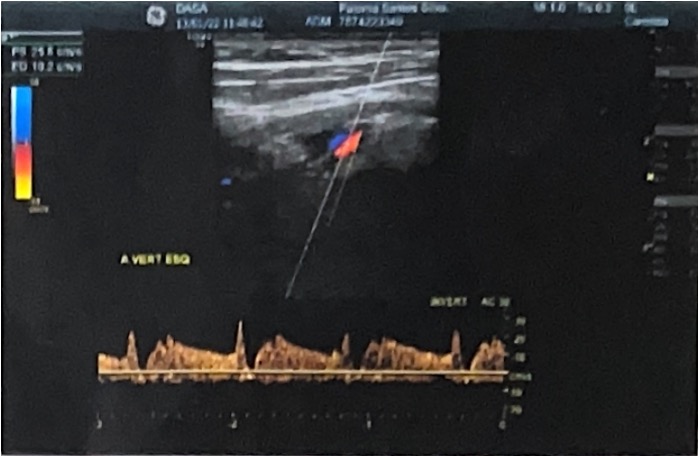

Takayasu's Arteritis and Double Right Renal Artery: A Previously Unreported Association

Mauer Alexandre da Ascensão Gonçalves, Humberto Morais, Miguel Bernardino Antunes Vicente, Capela Pascoal, Tshimbalanga Merite